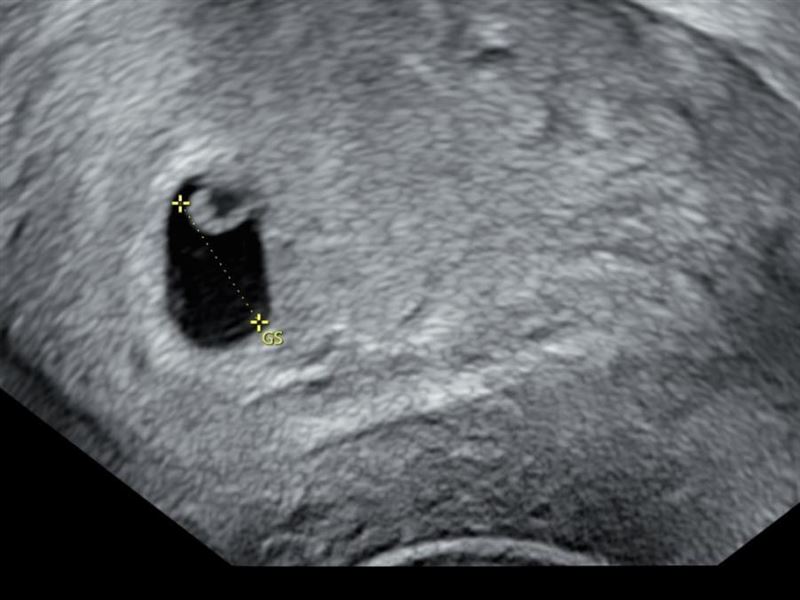

鄭家純表示,半個月前產檢發現胚囊發育晚了一週,醫生說有可能是排卵期晚一週,另一個可能就是胚胎有狀況,沒想到昨晚開始她就少量出血,過2小時後出血量變多開始腹痛,立刻去急診。她發文提到:「在醫院時陸續有排出血塊,照了陰道超音波確認胎囊大小與半個月前產檢時一樣,目前的處置就是回家休息吃止痛藥,等體力恢復後回台灣做後續。」讓網友紛紛留言為她打氣安慰。